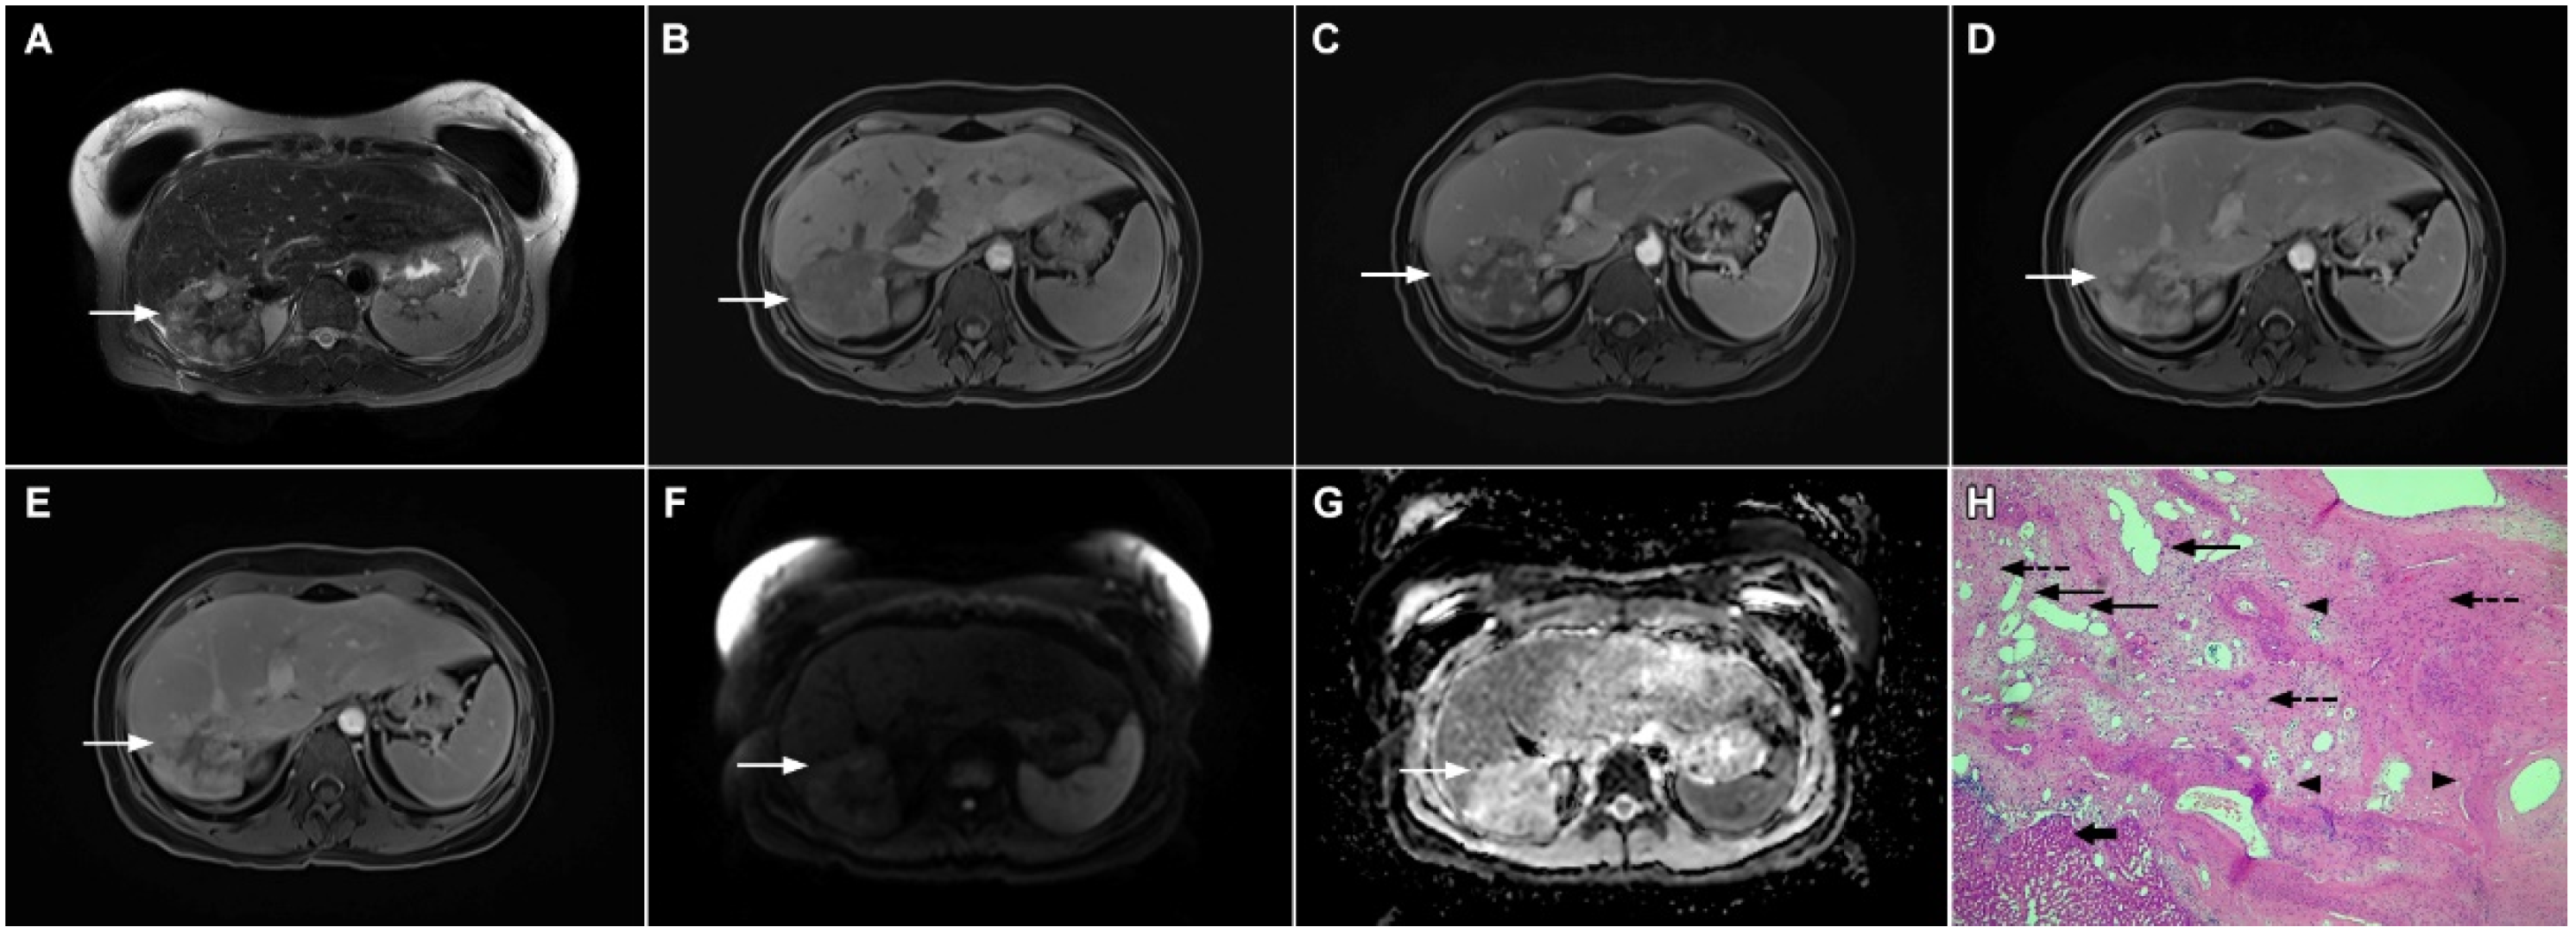

Figure 16.

Solitary hypovascular liver metastasis in a 59-year-old woman. A slightly hyperintense lobulated lesion (arrow) with capsular retraction is seen in liver segments VI and VII in the T2-weighted image (A). The tumor (arrow) is hypointense in the plain T1-weighted image (B) with a slight peripheral enhancement in the arterial phase (C) and a progressive central enhancement in the portal venous (D) and delayed phases (E). In the DWI (F) and corresponding ADC map (G), the tumor (arrow) shows targetoid appearance. Hematoxylin and eosin (H&E) staining showed well-differentiated adenocarcinoma cells of intestinal type (dashed arrow), and normal liver parenchyma adjacent to the metastasis (arrow); original magnification ×40 (H).